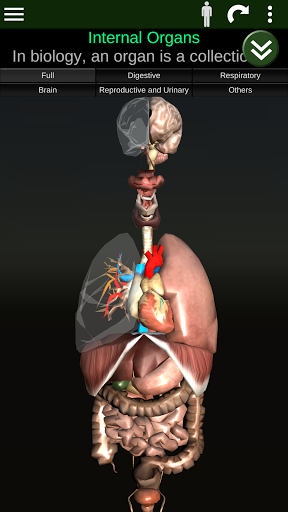

Menampilkan model anatomi 3D dari organ utama tubuh manusia dan penjelasannya masing-masing.

Apa yang ada di aplikasi?

* Sistem pencernaan, termasuk lambung, usus kecil, usus besar, dan animasi sistem ini.

* Sistem pernafasan, yang meliputi trakea, bronkus, paru-paru dan animasi sistem ini.

* Jantung, yang meliputi atrium, ventrikel, aorta, dan animasi organ ini.